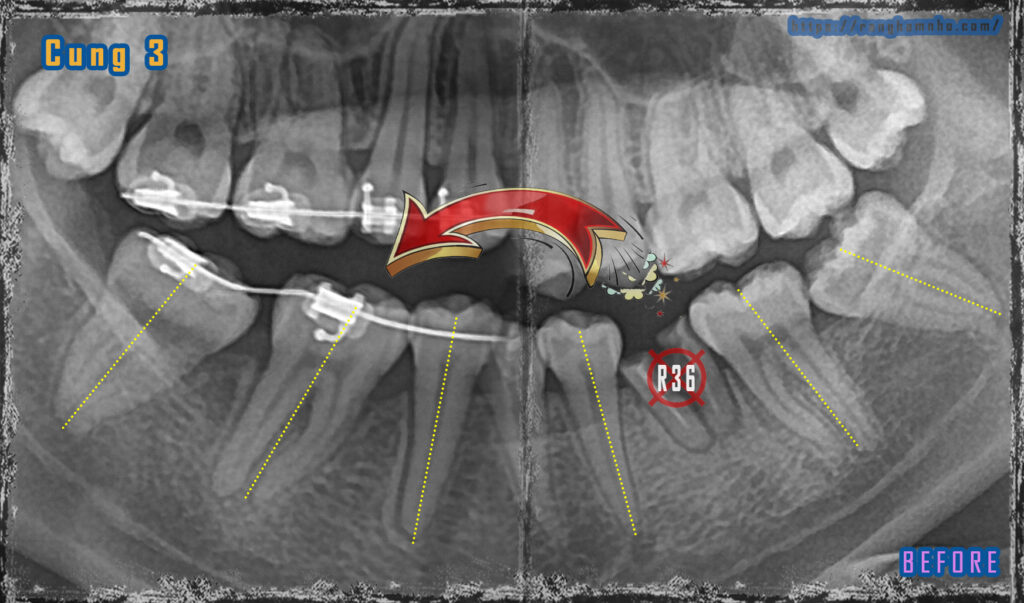

Bệnh nhân nữ không may có răng hàm lớn hàm dưới ở cả 2 bên phải (R36) và trái (R46) đều sâu vỡ lớn, chỉ còn chân răng. Hai chân răng đều có chỉ định nhổ, sau nhổ răng quyết định lựa chọn trồng răng implant hoặc niềng răng kéo di gần. Rất may và tình cơ BN đang mong muốn niềng răng cai thiện thẩm mỹ nụ cười, BN quyết định bỏ thời gian công sức cùng bác sĩ tiến hành di gần R7 về R6 và R8 về R7.

Hình ảnh Răng 36 được nhổ bỏ, R37 di về R36, R38 di về R37. Các trục răng song song- cả thân và chân răng đều dịch chuyển.